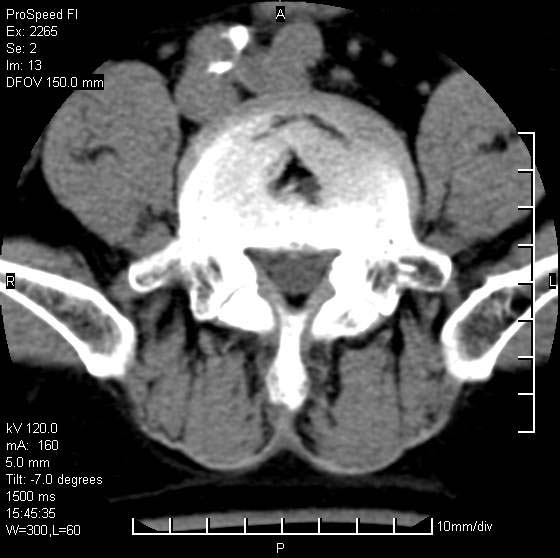

以下是引用qiushi在2007-8-22 17:26:00的发言:[br]没骨窗![br] 1、 l5~s1间盘膨出伴轻度突出(中央型)、变性。[br] 2、l4~5间盘膨出伴突出(右侧远外侧型)。[br] 3、l3~4间盘膨出。[br] 4、腰椎退行性变。[br]

以下是引用随缘的人在2007-8-22 20:56:00的发言:[br]腰椎退行性变:1。l4/5,l5/s1膨出[br] 2。l5/s1间盘退行性变 [br] 3。腰椎骨质增生

以下是引用liaizhi在2007-8-22 22:13:00的发言:[br]1,l4-5锥间盘膨出,2,l5-s1椎间盘膨出并退变(椎间盘呈真空征);3,血管瘤(椎体骨小梁稀疏粗大)?